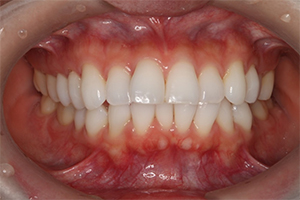

矯正治療のCASE 02

Before

After

- 主訴

- 上顎前歯が出ていて口が閉じにくい

- 治療内容

- 上顎前突・出っ歯の非抜歯による歯並び治療

- 治療費用

- 88万円~(税込)

- 治療期間

- 12ヶ月

【リスク・副作用】

歯の痛み、口内炎、歯磨きがしにくいことによるむし歯や歯周病のリスク、歯根吸収や歯の変色、後戻りなどの副作用があります。